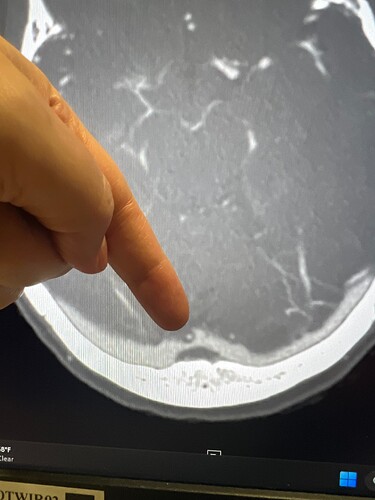

it is definitely possible to get symptoms and intracranial hypertension from an an arachnoid granulation compressing the venous system, especially if the dominant side is compressed. i had jugular decompression (right) surgery in february and felt worse not better after - the only lasting relief i got was brain fog improvement. recently they discovered i had an arachnoid granulation compressing my transverse sinus (right) with a gradient of 15 mmHg in my last venogram. and i just had it fixed by compressing it with a stent (the stent opens up the compression and compresses the arachnoid granulation, which then re-absorbs into the body). my arachnoid granulation was in a similar spot to yours and my venous pressures normalised after stent placement. my stent starts in the transverse sinus and extends through my torcular and into the sagittal sinus. as for symptom improvement i can’t say yet…it’s only been 5 days and i had complications during the surgery which are probably masking any improvements for now, but hopefully once i’ve recovered there will be some noticeable improvements. so far my pulsatile tinnitus remains despite 2 stents, and jugular decompression so that one is a real mystery.